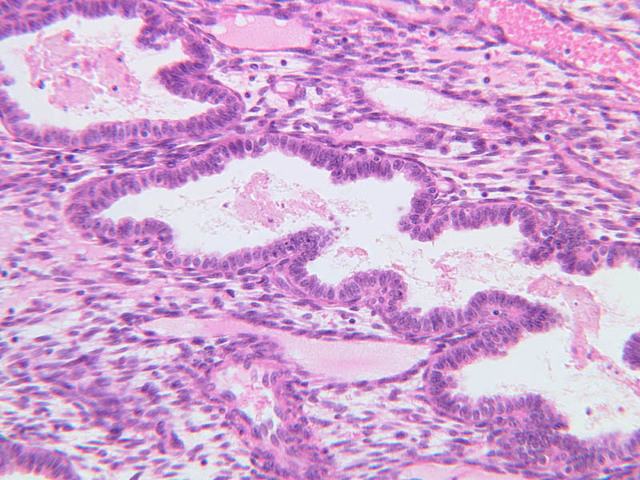

This phase occurs on days 15 to 27 and corresponds to the ovarian luteal phase characterized by rising levels of progesterone. The epithelial cells begin to secrete a mucoid fluid rich in nutrients, especially glycogen. The glands become highly coiled and folded and toward the end, very distended. The density of the stroma lessens as it becomes edematous. (slides B-99 [2.5x, 10x, 20x, 40x] [2.5x, 10x, 20x, 40x]; B-100 [1x, 2.5x] [2.5x, 10x, 20x, 40x] [2.5x, 10x, 20x, 40x])

The endometrium of the cervical canal does not slough during the menstrual phase. The glands in this region are relatively large and extensively branched. They are lined by a tall simple columnar epithelium very active in the secretion of mucus. Occasionally these glands become blocked forming Nabothian cysts. The transition of the epithelium of the cervix to that of the vagina is abrupt and is in the region of the external os. At this point, the cervical simple columnar is replaced by the vaginal stratified squamous epithelium (slide B-98 [2.5x-labeled, 10x, 20x, 40x] [2.5x, 10x, 20x, 40x]). This is an area which is commonly inflamed as well as a primary location of cervical cancer.